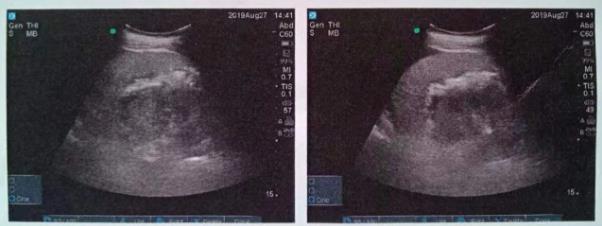

術(shù)后CT,箭頭所指為腎結(jié)石被徹底清除

三日后,曾奶奶病情逐漸穩(wěn)定,各項(xiàng)感染指標(biāo)逐漸恢復(fù)正常,復(fù)查CT顯示腎結(jié)石已經(jīng)被完全清除,現(xiàn)已康復(fù)出院。就此,困擾曾奶奶多年,反復(fù)感染差點(diǎn)致命的腎結(jié)石頑疾被徹底治愈。曾奶奶全家人對(duì)于愛(ài)康集團(tuán)泌尿外科專家高超的碎石取石手術(shù)技藝更是贊許有加,對(duì)泌尿外科團(tuán)隊(duì)的工作給予衷心感謝和高度評(píng)價(jià)。